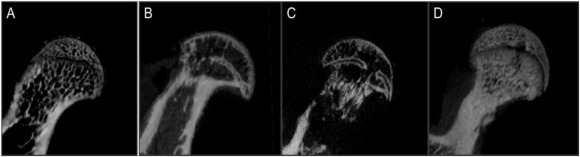

显微CT分析结果:四个组的所有32个样品均进行micro-CT扫描。 比较四组中各组的结果后,唑来膦酸治疗组,NS组和模型组的BMD(B),Tb.Th(D)和BS / BV(F)值显著不同。

图4、四组显微CT图像形态计量学评价:(A=正常组)骨小梁致密、连续、增厚,排列整齐;(B=模型组),(C=生理盐水组)局部结构消失,股骨头其他部位骨小梁不连续、紊乱,变薄,股骨头坏死较其他各组严重;(D=唑来膦酸治疗组)同一部位的小梁较模型组和NS组致密、连续,但少于正常组。(NS=生理盐水)。